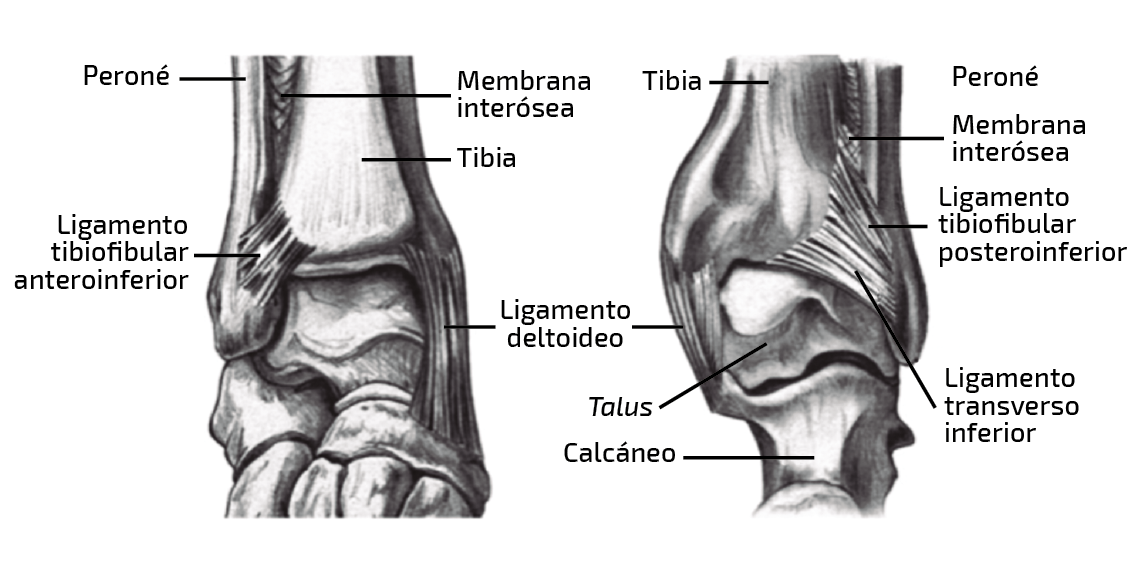

Las lesiones agudas se subdividen en (Figura 1):

- Estables: lesión del LTFAI, con o sin ligamento interóseo (LIO), y con un ligamento deltoideo intacto, además de ausencia de inestabilidad subjetiva.

- Inestables: incluyen lesiones del ligamento deltoideo y pueden ser divididas en latentes (existe compromiso del LTFAI con o sin lesión del LIO y lesión del deltoideo) y francas (existe lesión de los 4 ligamentos mayores y del ligamento deltoideo).

Figura 1. Anatomía.